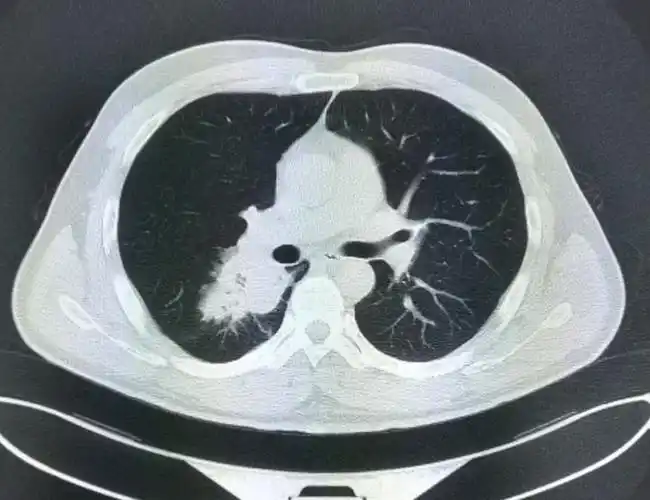

右侧中心型肺癌,右肺切除术后两年,术后残腔?——中心医院病例库